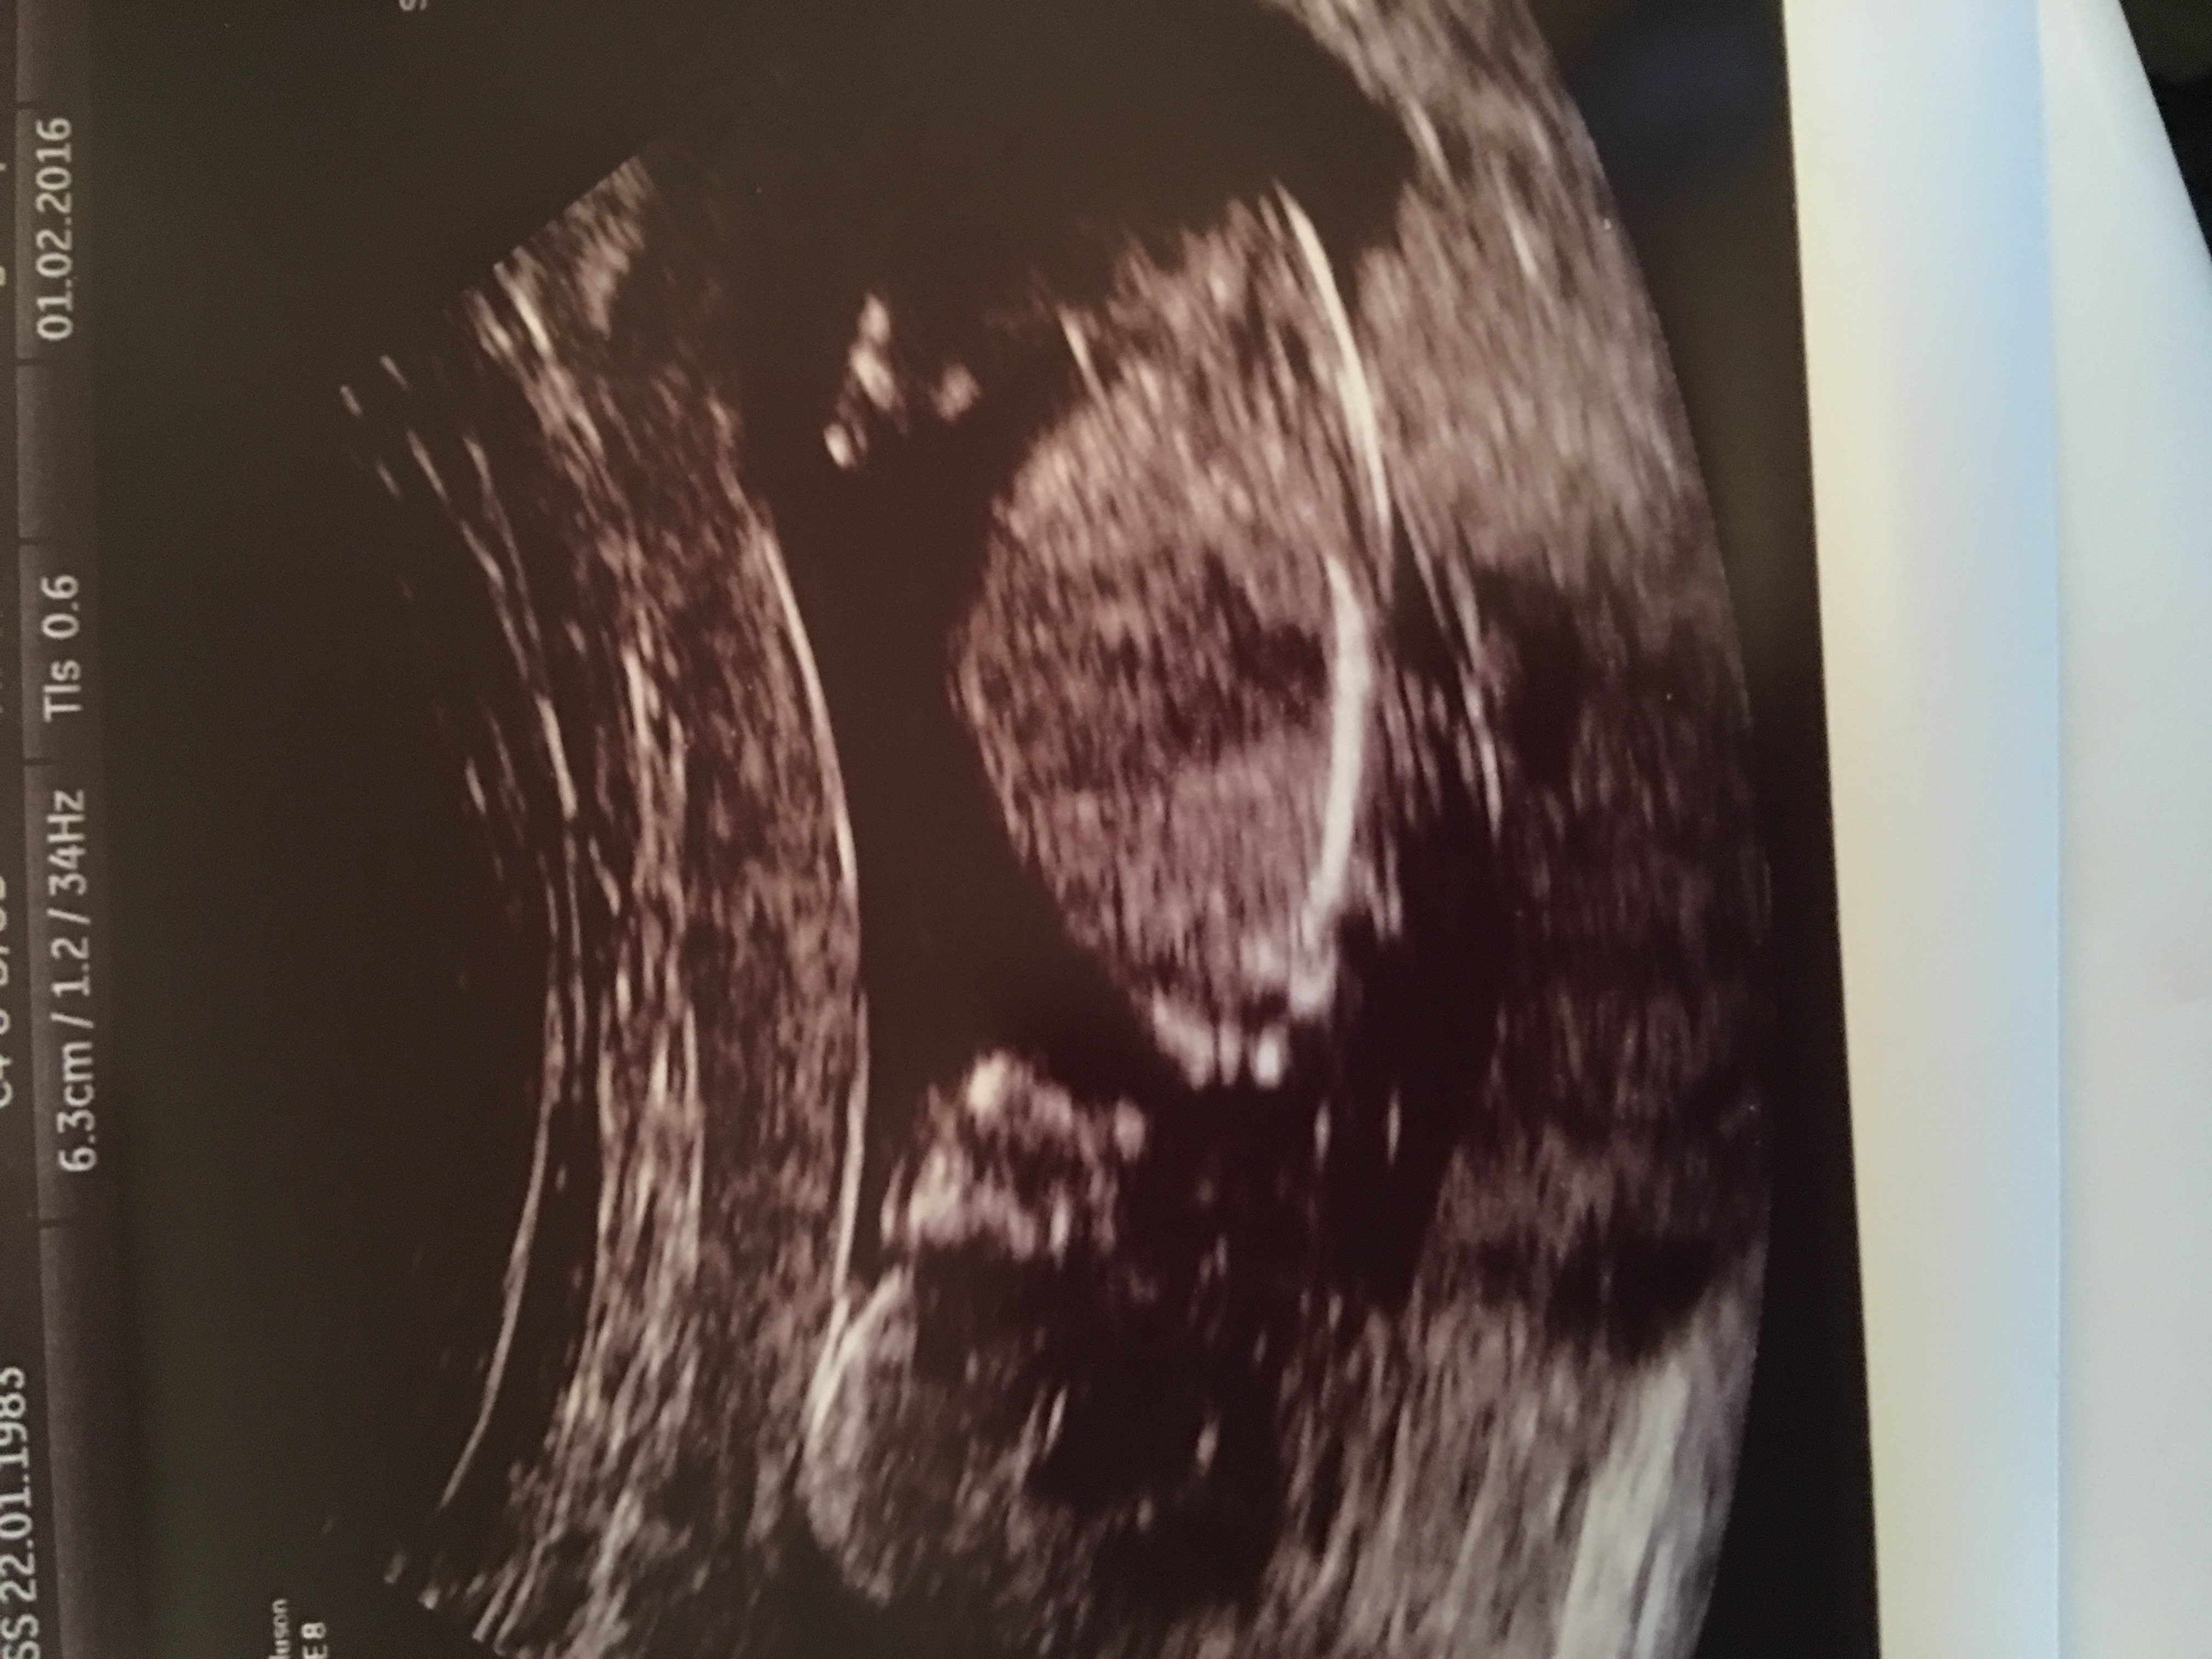

Girl lean.

Girl lean also

Maybe girl Sent from my GT-I9305T using Tapatalk